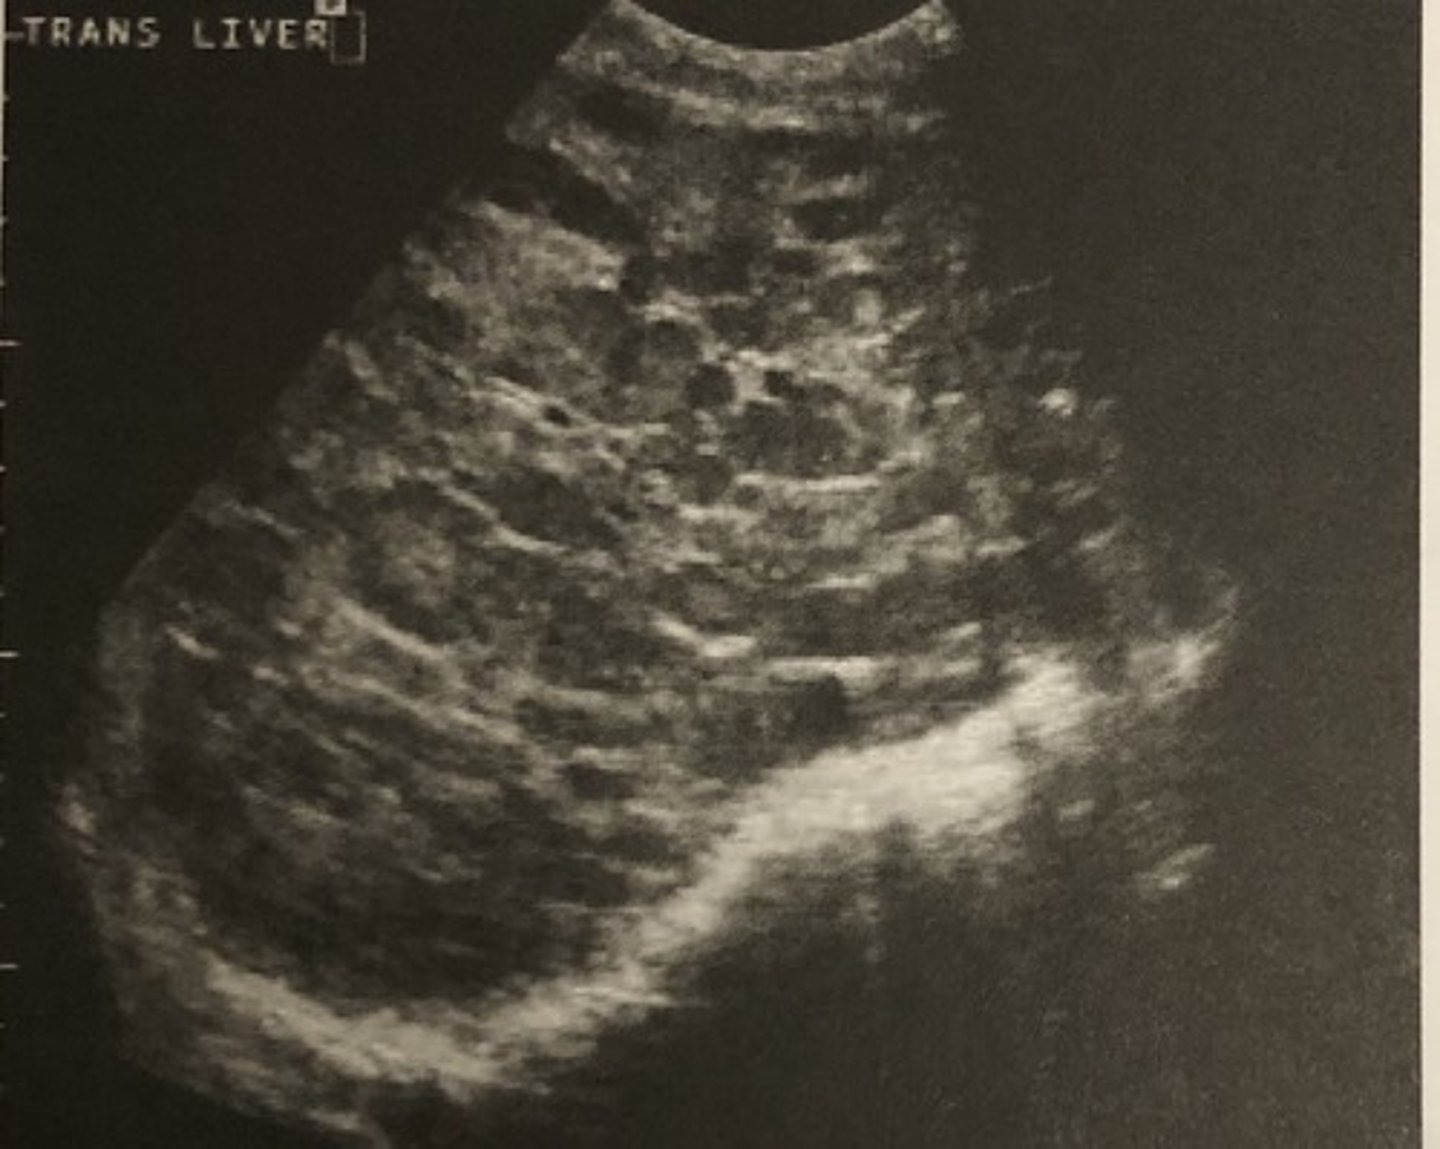

A. Metastatic liver disease

638. In the patient described in question 636, evaluation of her right upper quadrant indicates:

B. Liver abscess

C. Normal liver

D. Abdominal ascites

E. Perihepatitis